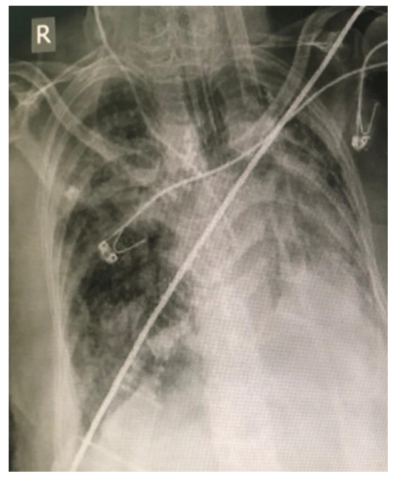

A 59-year-old female was referred to emergency department of Imam Reza hospital, Mashhad, Iran due to slowly progressive lower legs erythema and edema, as well as nausea, vomiting, stomach ache, constipation, malaise and myalgia within two previous weeks. Her medical history was notable for a completely treated pulmonary tuberculosis 8 years ago. Due to deterioration of general condition and progressive dyspnea, she was admitted in COVID-19 zone of the hospital suspicious to atypical presentation of COVID -19. During the hospitalization, blood oxygen saturation level was decreased to 70% and thus, she was admitted to intensive care unit (ICU). Lung High-Resolution computed tomography (HRCT) and chest x-ray revealed bilateral lung involvement which was more severe at the right side (fig1 and 2). Laboratory data are summarized in table 1.

Figure 1: Chest radiography of COVID-19 patient with pseudocellulitis lesions in legs (AP technique). Reticular pattern and linear atelectasis bands in right lung field and consolidation in lower lobe of left lung is visible